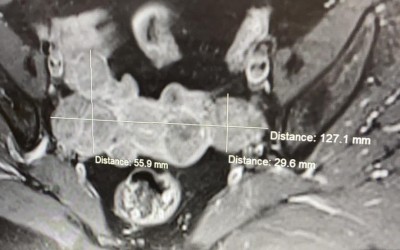

Un caz dificil a fost rezolvat cu succes prin interventie chirurgicala minim-invaziva, de catre dr. ZDREHUS RAZVAN, medic primar la sectia de Obstetrica-Ginecologie. Pacienta are varsta de 50 de ani, este din zona Marghitei si primele simptome spune ca i-au aparut in urma cu aproximativ cinci ani. PACIENTA: „Eu am mers regulat la medic pentru control, investigatii, mi-am facut inclusiv...